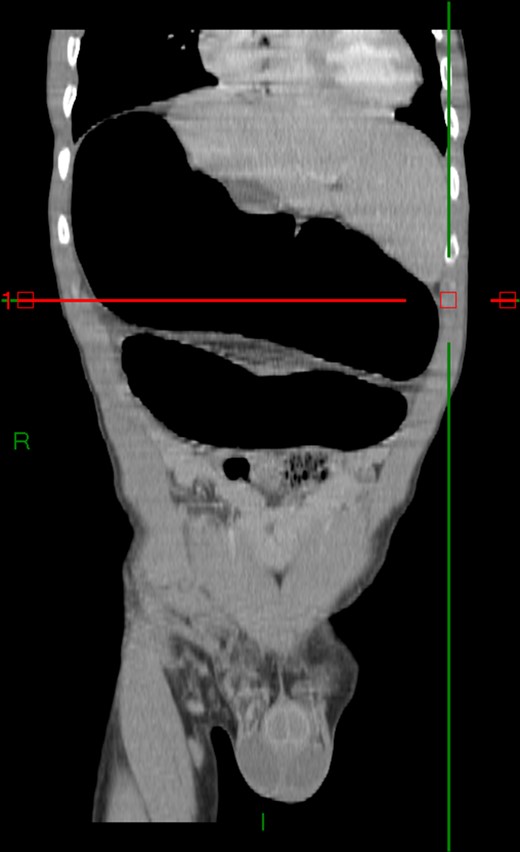

Case 2: A 92-year-old women, without previous abdominal surgery or history of abdominal trauma or peritoneal infections was admitted to the emergency department with generalized abdominal pain. Physical exam revealed markedly distended abdomen with generalized abdominal pain with tenderness. Laboratory investigation on admission: white cell count of 30.200/mm3 with 84.7% neutrophils, protein C reactive of 13.6 mg/dL and lactates of 2.17 mmol/l. Abdominal X-ray showed a marked colonic enlargement. Abdominal-pelvic CT identified a colonic volvulus associated with a transmesocolic hernia with transmural necrosis of the colon sigmoid (Figs 2 and 3). The patient was proposed to laparotomy during which a volvulus of colon sigmoid with transmural necrosis in a strangulated transverse transmesocolic and transomental (great omentum) hernia was identified (Figs 4 and 5). A Hartmann procedure was conducted and the patient was discharged at fifth post-operative day. At 3 months follow-up consultation, the patient remained free of complains.

Abdominal-pelvic CT—coronal plane: colonic volvulus associated with a transmesocolic hernia with transmural necrosis of the colon sigmoid.